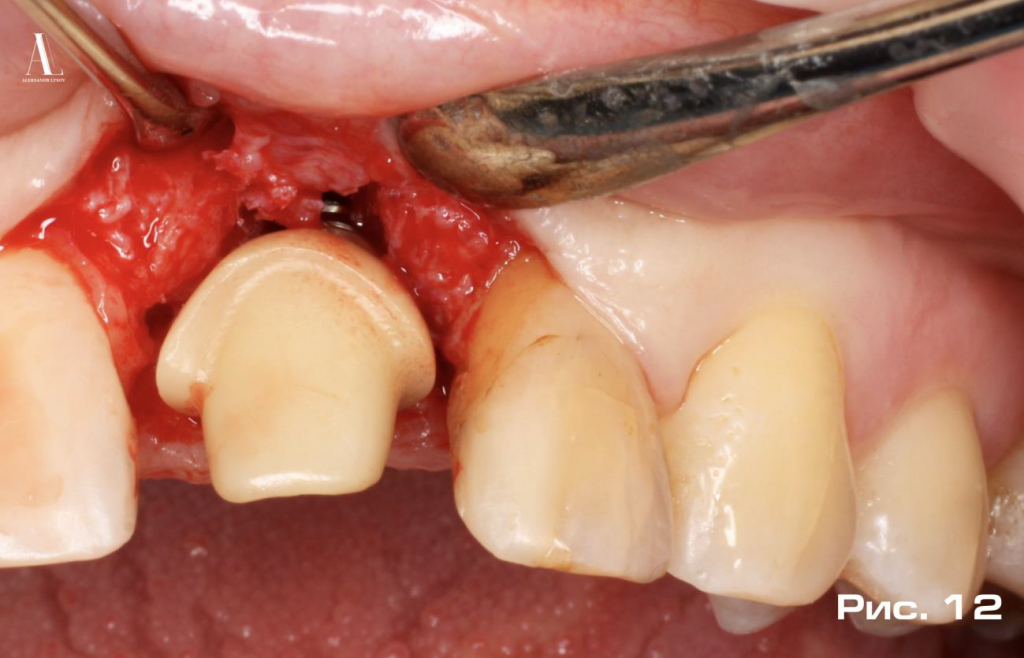

К только что установленному имплантату фиксируется заранее изготовленный индивидуальный постоянный абатмент с усилием 35 н/см (Рис. 12).

Важно отметить, что абатмент устанавливается один раз и больше никогда не извлекается из имплантата. Благодаря этому согласно экспериментальным (Abrahamson, Berglundh et al. - 1997), литературным (Tallarico M, Caneva M et al. - 2018) и клиническим (Linkevicius T et al. - 2010-2020) исследованиям удается исключить травмирование защитной мягкотканной буферной зоны на этапах протезирования, что в свою очередь предотвращает резорбцию костной ткани в области платформы дентального имплантата. Одномоментный абатмент, в качестве каркаса, способствует образованию избыточного объема мягких тканей и дополнительного пространства для аугментации между субгингивальной частью абатмента и мукопериостальным лоскутом.